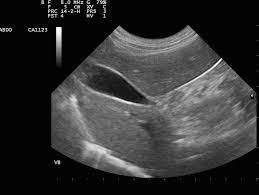

Exploration des pathologies des seins et des masses ou collections des parties molles.

Exploration de la thyroïde, des parathyroïdes, des ganglions et des parties molles du cou.

Examens spécialisés pour les enfants et les nourrissons (Écho transfontanellaire - ETF, hanches).